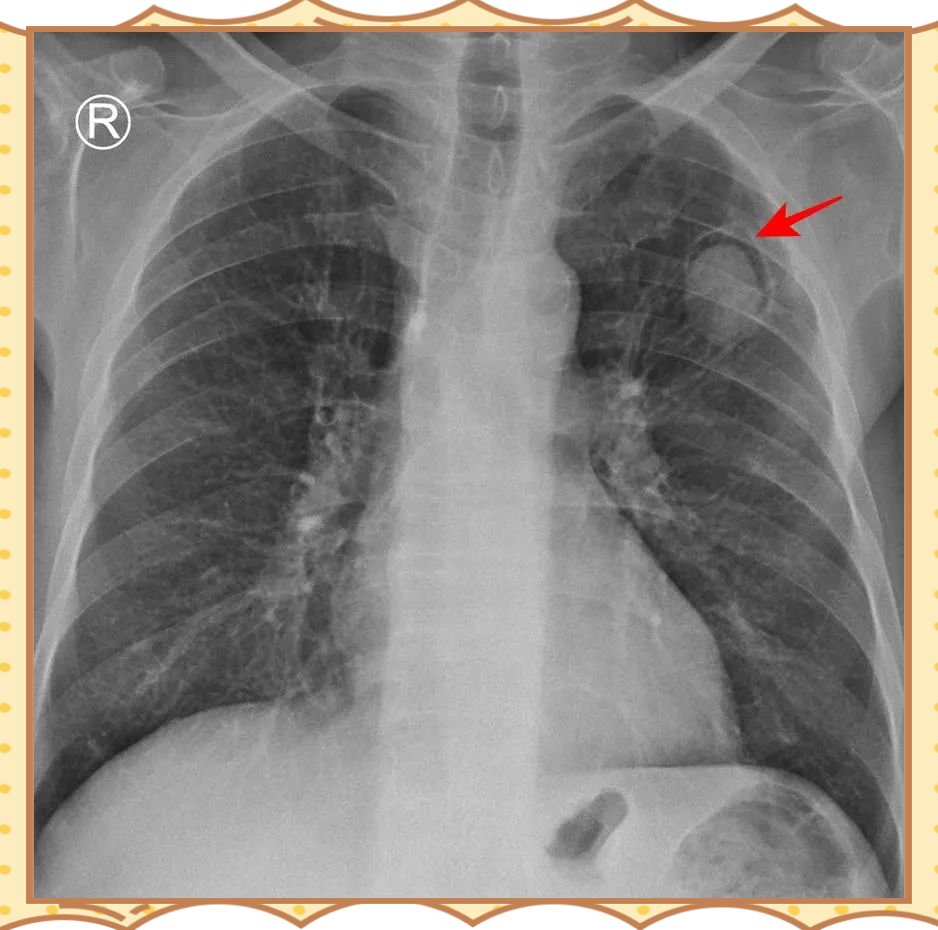

肺炎的症状及治疗方法

症状差异与个体因素密切相关年龄基础疾病病原体类型如细菌病毒真菌及感染部位如大叶性肺炎支气管肺炎均会影响症状组合例如,老年人可能以低热意识障碍为主,儿童易出现高热惊厥治疗与护理要点轻症患者通过抗生素细菌性肺炎或抗病毒药...